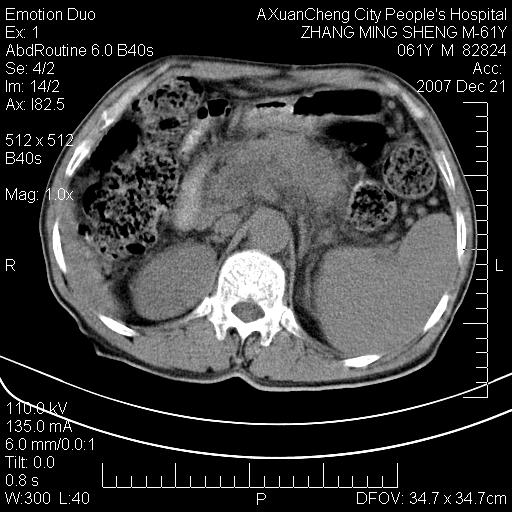

标题: CT11031:M61Y,胰腺占位 [打印本页]

标题: CT11031:M61Y,胰腺占位

大家侃侃门静脉和胆管系统怎么回事,肝内转移?

胰腺癌肝转移

肝硬化,门脉高压,脾肿大;弥漫性肝癌,肝内、门脉、腹膜后淋巴结转移,肝内外胆管扩张,胰头区占位,建议mr检查

胰腺癌伴肝内转移;门脉、肠系膜上v癌栓形成。

考虑为:胰腺癌伴肝脏转移、腹膜后淋巴结转移,门静脉及肠系膜上静脉瘤栓形成。

胰体尾癌伴肝内转移,门静脉及肠系膜上静脉瘤栓形成.

肝硬化,脾大. 胰腺癌伴肝内转移;门脉、肠系膜上v癌栓形成。